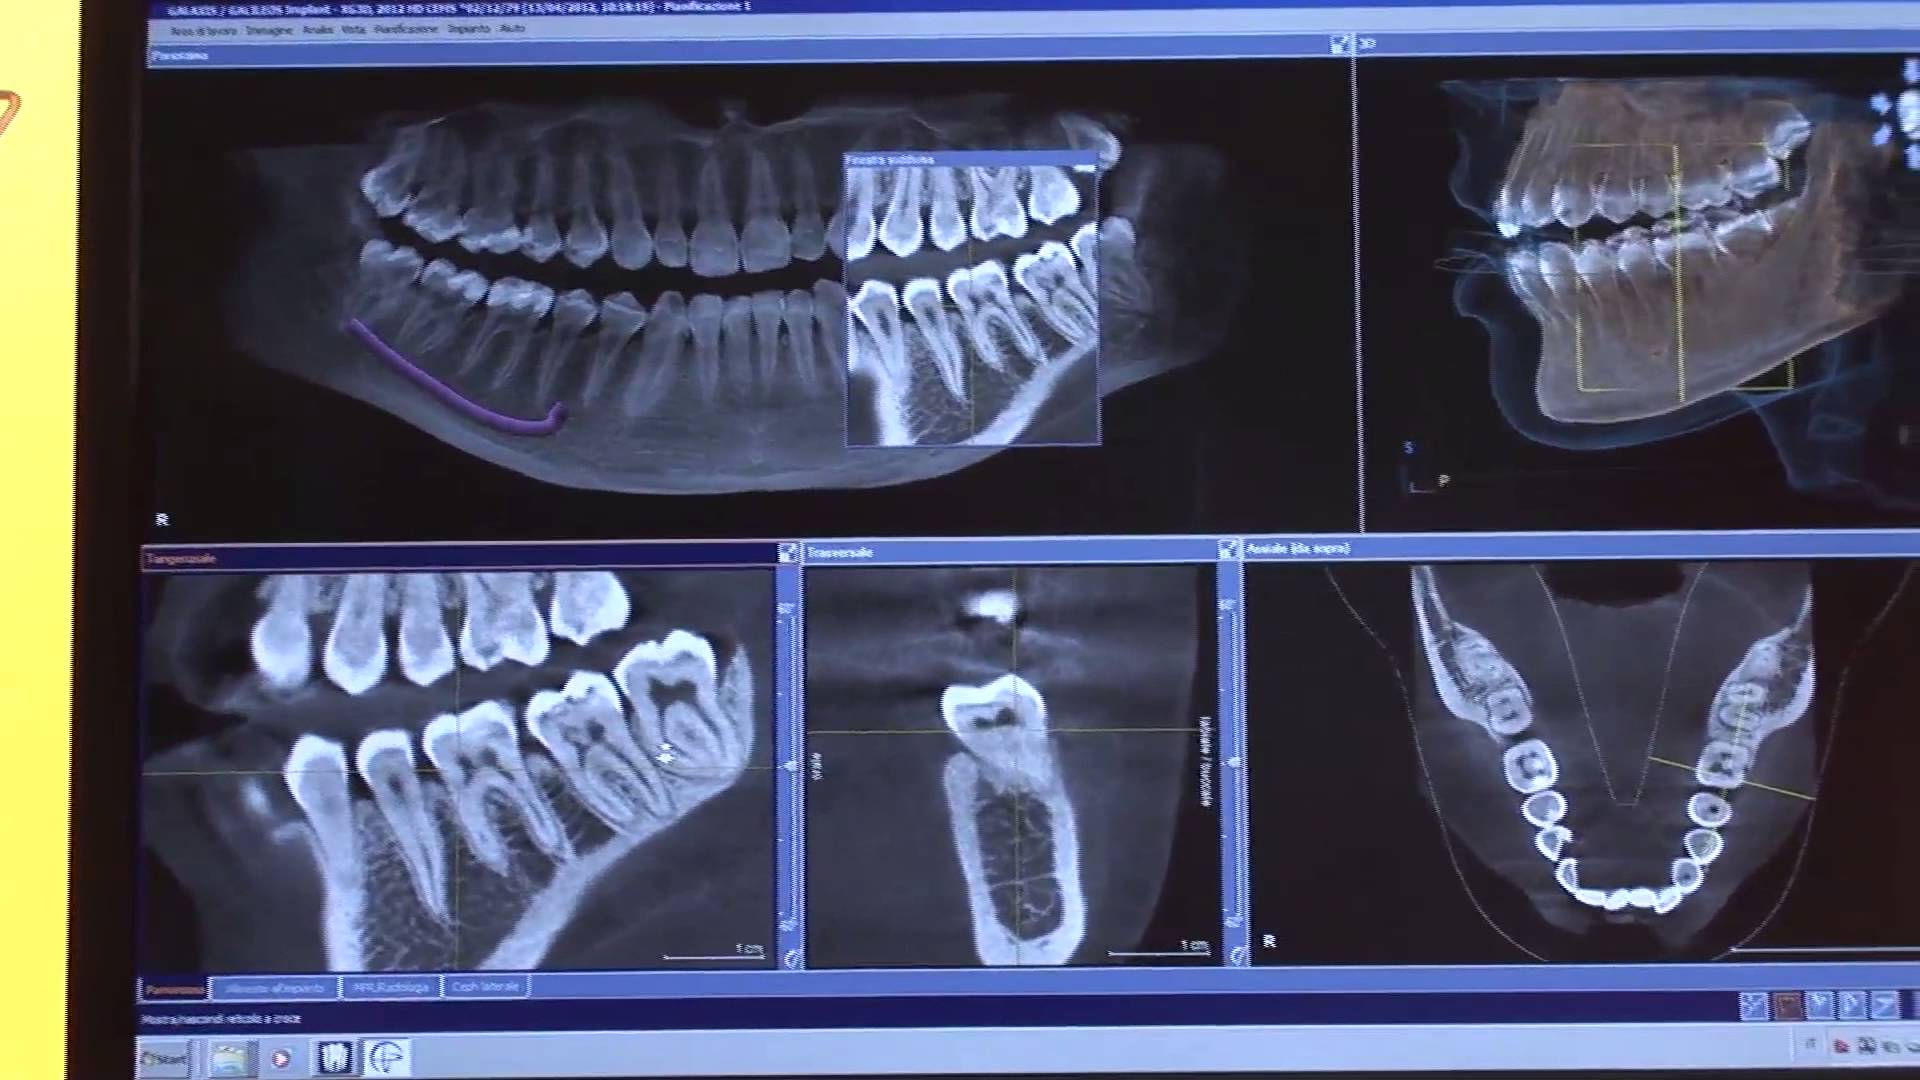

ORTHOPHOS XG 3D se adapta con precisión a las rutinas diarias de las prácticas dentales privadas: puede capturar la mandíbula entera del paciente en un solo espacio . El campo de visión es lo suficientemente grande como para evitar las repetidas exposiciones a radiografías innecesarias dado que las imágenes son en 3D. Además de ser lo suficientemente pequeño como para ahorrar en tiempo para el diagnóstico.

Siempre que necesitemos ver más, el módulo 3D proporciona mayor seguridad pero la modalidad estándar en 2D de ORTHOPHOS XG 3D, con amplios programas de rayos X panorámicos y cefalométricos, ofrece la imagen de rayos X que necesitamos.